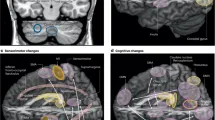

Наблюдение и имитация движений рук при болезни Паркинсона: в...

Введение в проблему болезни Паркинсона Болезнь Паркинсона (БП) представляет собой нейродегенеративно...